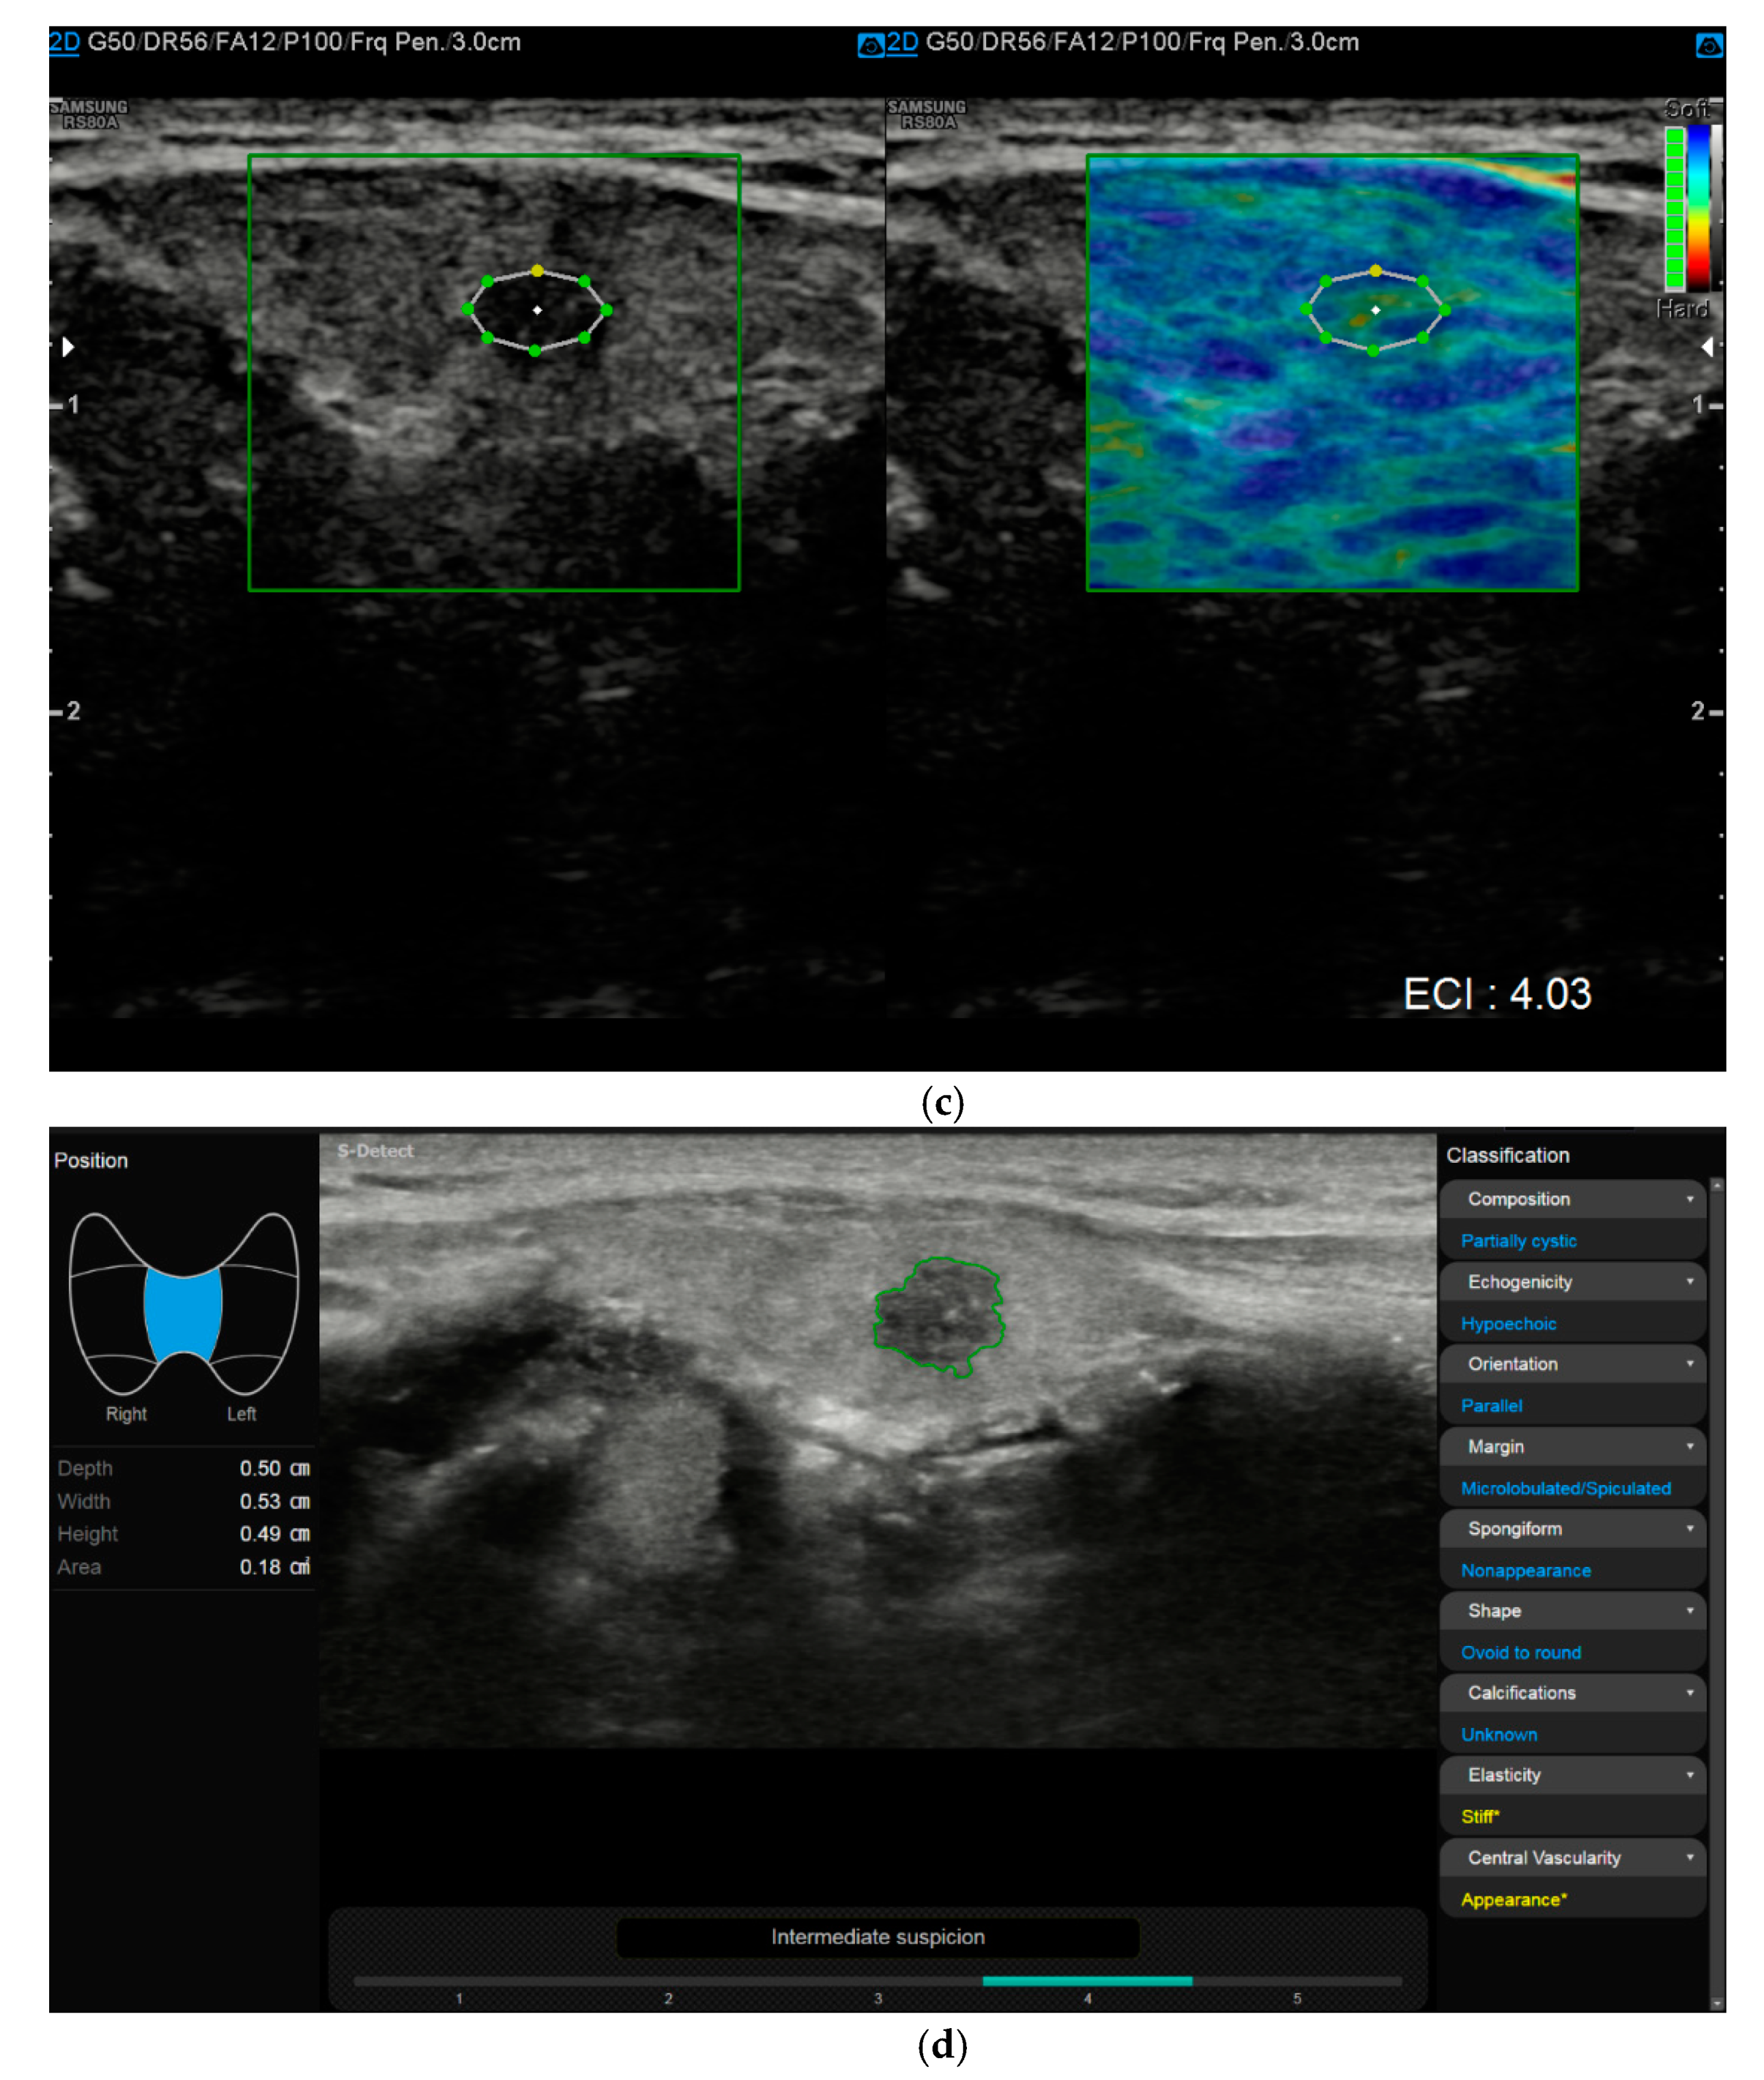

6. Multiparametric Ultrasound

Multiparametric Ultrasound (MPUS) Role for Indeterminate Thyroid Nodule Evaluation